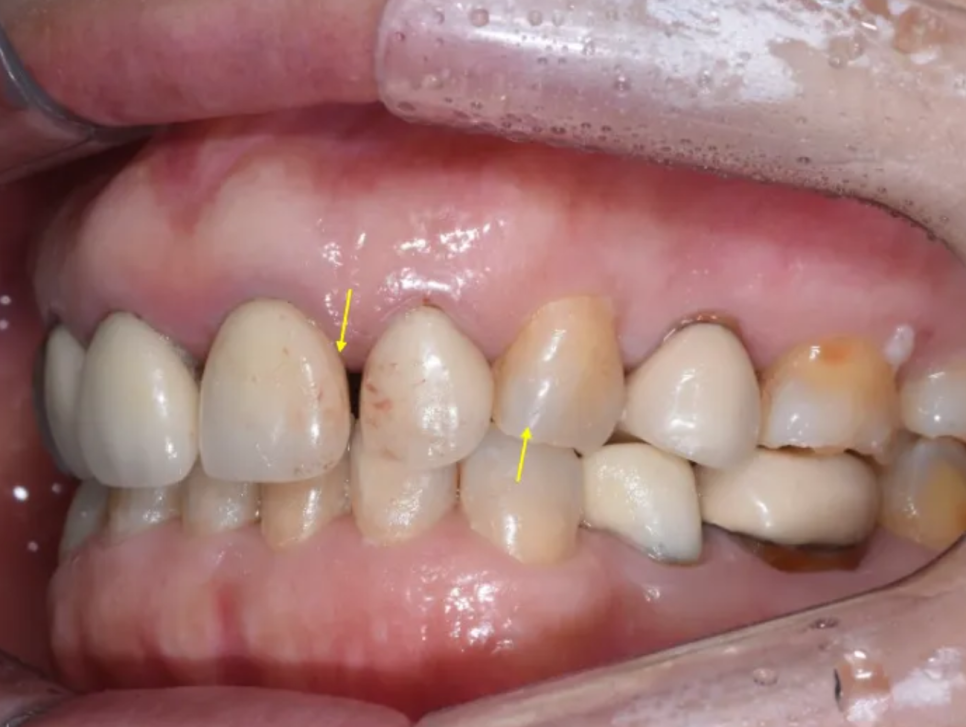

구내 검사 – 기존 크라운과 치아 상태의 문제점들

입 안을 자세히 살펴보니, 문제점이 한두 가지가 아니었습니다. 정리하면 다음과 같습니다.

| 기존 크라운 상태 | 오래된 도재-금속(PFM) 크라운의 마진 부적합, 변색, 치아 간 색상 부조화 |

| 앞니 사이 공간 | 가운데 두 앞니 사이, 그리고 왼쪽 앞니들 사이에 벌어진 공간 존재 |

| 오른쪽 송곳니 | 변색, 잇몸 쪽 마모(법랑질 닳음), 잇몸 퇴축 |

| 왼쪽 송곳니 | 절단면(끝부분)이 닳아 있는 상태 |

| 양쪽 송곳니 공통 | 치아 축이 안쪽으로 과도하게 기울어져 있음 |

| 블랙트라이앵글 | 오른쪽 앞니-작은앞니-송곳니 사이에 검은 삼각형 공간 존재 |

| 정중선 | 위아래 치아의 가운데 선이 맞지 않는 상태 |

한마디로, 심미적으로 개선해야 할 부분이 아주 많은 케이스였습니다. 일본의 치과에서 거절당하셨던 이유도, 기존 치아의 심한 손상 상태(포스트+코어)와 더불어, 이런 복합적인 문제들 때문이었을 것으로 추측됩니다.

앞니 사이 아주 큰 공간이 있고, 환자분 기준 우측 송곳니는 변색이 아주 심합니다

송곳니는 안쪽으로 많이 기울어져 있습니다

치아 사이 공간(블랙 트라이앵글)도 심한 편입니다

치아 사이 공간이 보이고, 송곳니가 많이 닳아 있습니다